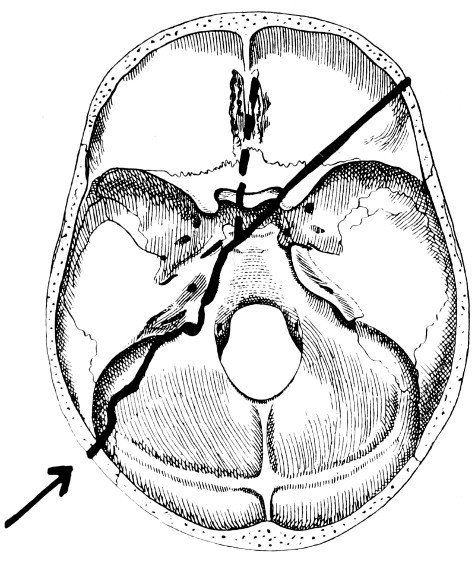

30. Plan of the base of the skull 77

31. To illustrate the relation of basic fractures to cranial nerves 81

32-37. The lines pursued by basic fractures 83-8